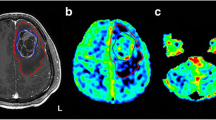

CBF and CBV parametric maps were computed by using a proprietary software suite including a “perfusion-weighted imaging” toolbox that was installed on a dedicated multimodality workstation (Siemens Medical Solutions, Erlangen, Germany). DTI data were processed by using the Diffusion II toolbox [extension to SPM (http://www.fil.ion.ucl.ac.uk/spm/ext/#Diffusion_II)]. Grayscale maps for FA, radial diffusivity (RD), and axial diffusivity (AD) were computed after correcting the time series for motion, reorienting gradients accordingly, computing the tensor regression, and then computing the tensor decomposition. The affine registration parameters to register the FA, RD, AD images to the 3D T1 image were computed from the standard SPM mutual information-based registration of the respective b = 0 image to the T1 reference. After the parametric maps of CBF, CBV, FA, RD, and AD were registered to the T1 reference images of each patient, cGM and cWM parameters were evaluated within each cerebellar hemisphere after masking with the binary segmentation of the cerebellar tissues of interest (Fig. 1).

Post-operative axial T2-weighted images of the supratentorial lesion area (a) and cerebellum (b). Axial 18FDG PET images of the cerebellum, showing decreased metabolic activity within left cerebellar cortex consistent with diaschisis (c). Axial parametric maps of FA (d), CBV (e), and CBF (f). All images are of the same patient (#5)